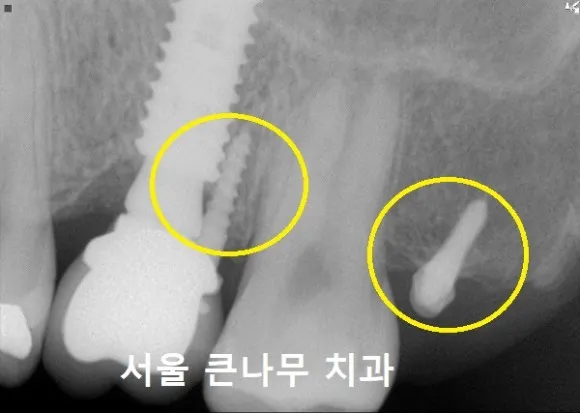

한 달 뒤 체크 후 연결 체인을 교체해 주었습니다.

2개월 차

다시 한 달 뒤 체인을 교체해 주었습니다. 부분 교정 시작한 지 불과 2개월 뒤이지만 신기하게도 치아가 많이 당겨진 모습입니다